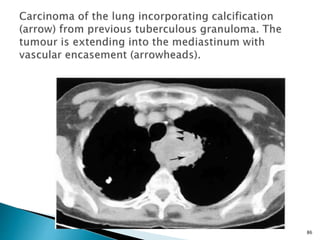

 Certain types of radiographically visible

calcification, such as lamellated or central

calcification in granulomas, and the

popcorn pattern in hamartomas, are highly

specific for benignity.

 Caution must be exercised, however, as a

growing lung cancer may surround a

calcified granuloma.

 CT can better detect and evaluate

calcifications within a nodule.

 The distribution of calcium, rather than its

presence alone, is a more important

diagnostic consideration.

84

 Thin layers of calcium in a lamellar pattern

are indicative of a granuloma, and popcorn

calcifications with associated fat density,

are associated with a benign hamartoma.